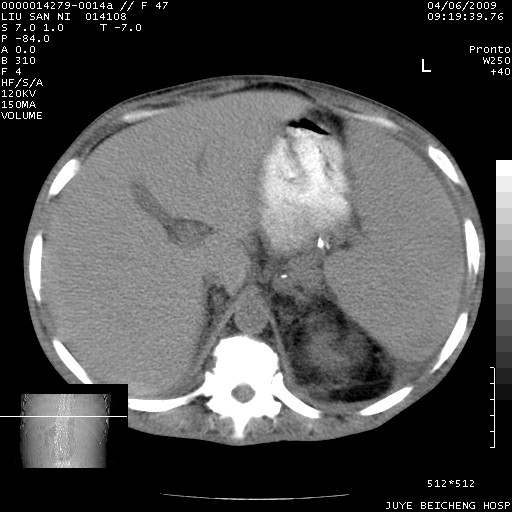

以下是引用前行在2009-4-7 10:31:00的发言:[br]肝脾肿大;双肾增大,双肾盂少量积水可能,肾膜膜增厚,肾周间隙增宽,并见桥间隔,提示结缔组系统疾病、系统性红瘢狼疮肾可能性大。继发右侧胸腔、心包、腹腔积液。

以下是引用深泽交通医院在2009-4-7 11:21:00的发言:[br]双侧肾周密度增高,见条索影,右肾实质见点片状低密度区,考虑弥漫肾炎【自身免疫性?】;;肾性水肿征